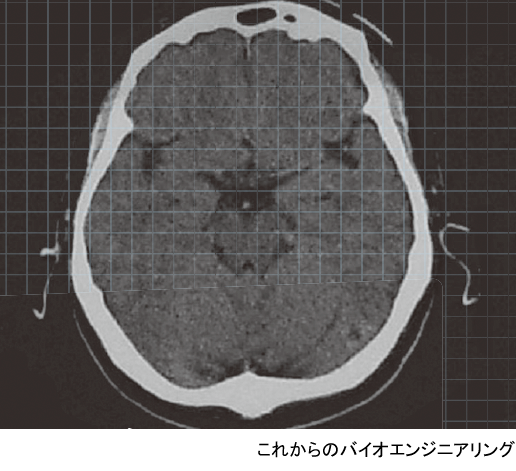

一方,右は脳内の構造をMRI(magnetic resonance imaging:核磁気共鳴イメージング)によって得た画像である.眼球より少し上の水平面で見たものである.大きな面積を占める灰色の部分が脳であり,白い頭蓋の中に納まっている.中心付近には視床などの間脳や脳室があり,生命活動の基本を支えている.その外側の頭蓋に近いところは大脳皮質と呼ばれ,ヒトの高度な情報処理機能はここを中心に行われている.大脳皮質は2次元的な広がりを持ち,それが折りたたまれるようにして頭蓋内に納められている.いわゆる,脳の